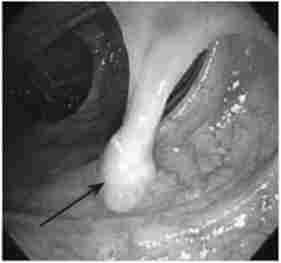

За допомогою колоноскопа на одній зі стінок кишки можна визначити освіту округлої або овальної форми з гладкою рожевої поверхнею (аденома), м'якої консистенції, на ніжці або без неї (рис. 14.2).

Ендоскопія дозволяє виявити поліпи розмірами до декількох міліметрів, тому можна розглядати дану процедуру не тільки як діагностичну, але і як лікувальну.

Аденоматозний поліп сигмовидної кишки на ніжці (фіброколоноскопії)

Мал. 14.2. Аденоматозний поліп сигмовидної кишки на ніжці (фіброколоноскопії)